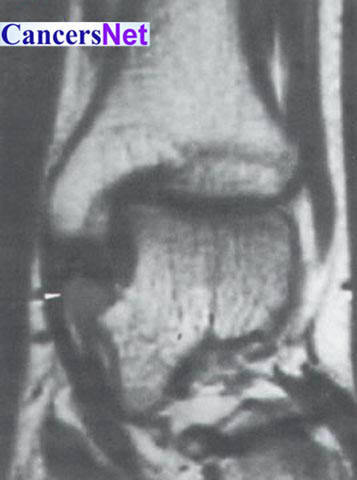

腱鞘巨细胞瘤